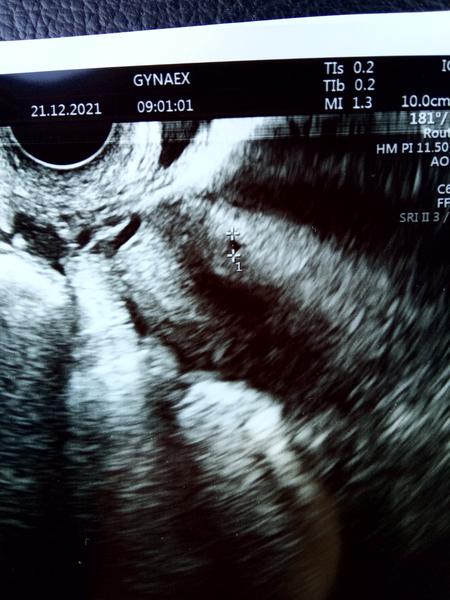

Takze bola som u ineho lekara. .povedal ze podla maternice sa jedna o jednoznacne tehotenstvo. Nasiel nieco co vyzeralo ako gestacny vacok 4mm ale nebol si isty lebo ze velmi malinke to je a blizko jazvy po cisarskom.vzal mi hcg a uvidime podla vysledkov ci bude nizsie a bude zodpovedat velkosti gest. Vacku alebo bude vysoke a budeme musiet tehu hladat mimo maternice. Zajtra budem mudrejsia...ale teda od tej svojej pojdem prec. Ta mi povedala po utz zo spodu ze nic nenasvedcuje tomu ze som tehotna...

No takze krv z pondelka 5+3tt je hodnota hcg 1500... Myslite ze je to ok? Vzali mi zasa krv teraz a poobede mam pisat pre vysledky a ze vraj ma byt dvojnasobne vyssie hcg aby to bolo ok. Teraz cakam na sono o 8.30 ci uvidi aj ta moja lekarka